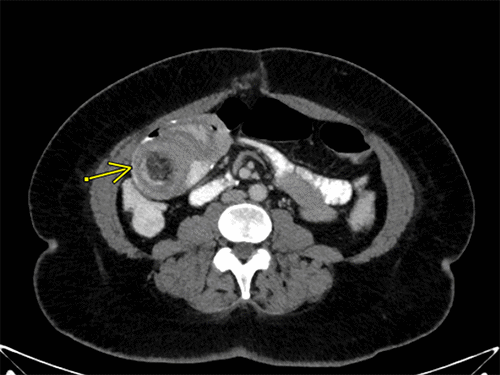

Figure 1. CT Scan Demonstrating Intussusception. Published with Permission

Nine years post-RYGB, the patient presented to the ED once again with complaints of intermittent abdominal pain for one week. Notably, she did not report experiencing nausea, obstipation, or abdominal distention. Upon presentation, her BMI was 32.5, and her vital signs were stable. During the abdominal examination, periumbilical tenderness was noted. Laboratory tests revealed a white blood cell count (WBC) of 7300/mcl; electrolyte levels were within the normal range. A CT scan (Figures 2 and 3) showed a small bowel intussusception involving the ileum, spanning approximately 20 cm, with signs of partial obstruction. Subsequently, the patient underwent a diagnostic laparoscopy, which revealed retrograde intussusception of the common channel at the anastomosis. Fortunately, the intussusceptum was easily reducible, and there were no indications of necrosis or edema. No bowel resection or enteropexy was deemed necessary. Following the procedure, the patient experienced an uneventful postoperative recovery, and she was discharged on POD 1.

Figure 3. Axial CT Image Demonstrating Intussusception at Second Presentation. Published with Permission